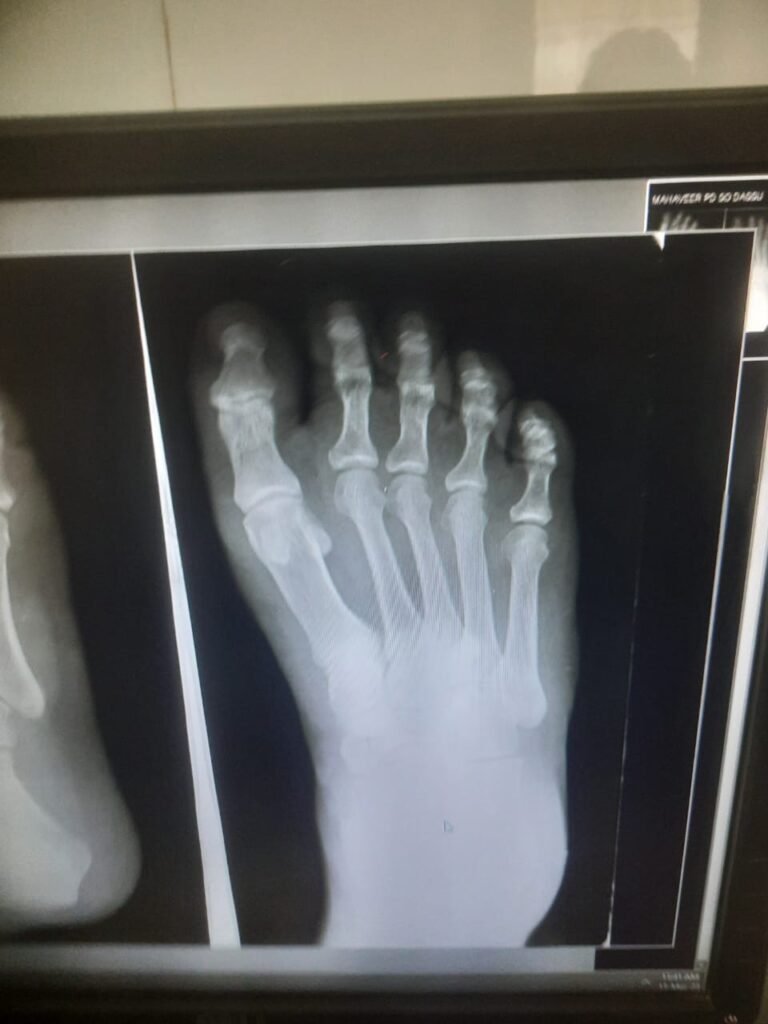

ऐसा ही मामला 31 तारीख का है उसे दिन इटारसी नरेंद्र नगर के निवासी महावीर बड़कुर जी अपनी पुत्री को को रेस्टोरेंट द पार्क में अपनी स्कूटी से छोड़ने जा रहे थे तभी उनकी स्कूटी रोड के मध्य में गैप में फंसने के पश्चात उनका ओवर ब्रिज पर एक्सीडेंट हुआ और स्कूटी भी क्षतिग्रस्त हो गई और ना ही कोई बीमा क्लेम मिला,, जिससे उनको पैरों में फ्रैक्चर अंदरुनी चोटे लगी हैं जिनका इलाज पूर्ण रूप से नहीं मिल पा रहा है और शहर के प्रतिष्ठित चिकित्सालयों ने आयुष्मान कार्ड से इलाज करने से मना कर दिया अब एक मध्यम वर्गीय रोज काम के खाने वाले शहर के नागरिक अपना इलाज शासकीय चिकित्सालय में ही करवा रहे है तत्कालीन स्थिति यह है कि अगर दोषी किसको ठहराया जाएगा तो किसे ,,ब्रिज बनाने वाले ठेकेदार को या पीडब्ल्यूडी के अधिकारी को या इलाज के नाम पर लूटने वाले शहर के प्रतिष्ठित डॉक्टरों को आखिर परेशान तो गरीब आदमी ही होता है जबकि उक्त नागरिक आयुष्मान कार्ड धारक है उसका इलाज शहर के किसी भी बड़े अस्पताल में भी हो सकता है लेकिन स्थिति यह है कि शहर में आयुष्मान के नाम पर जो लूट मची हुई है उसके मध्य नजर भी इलाज नहीं हो पा रहा है